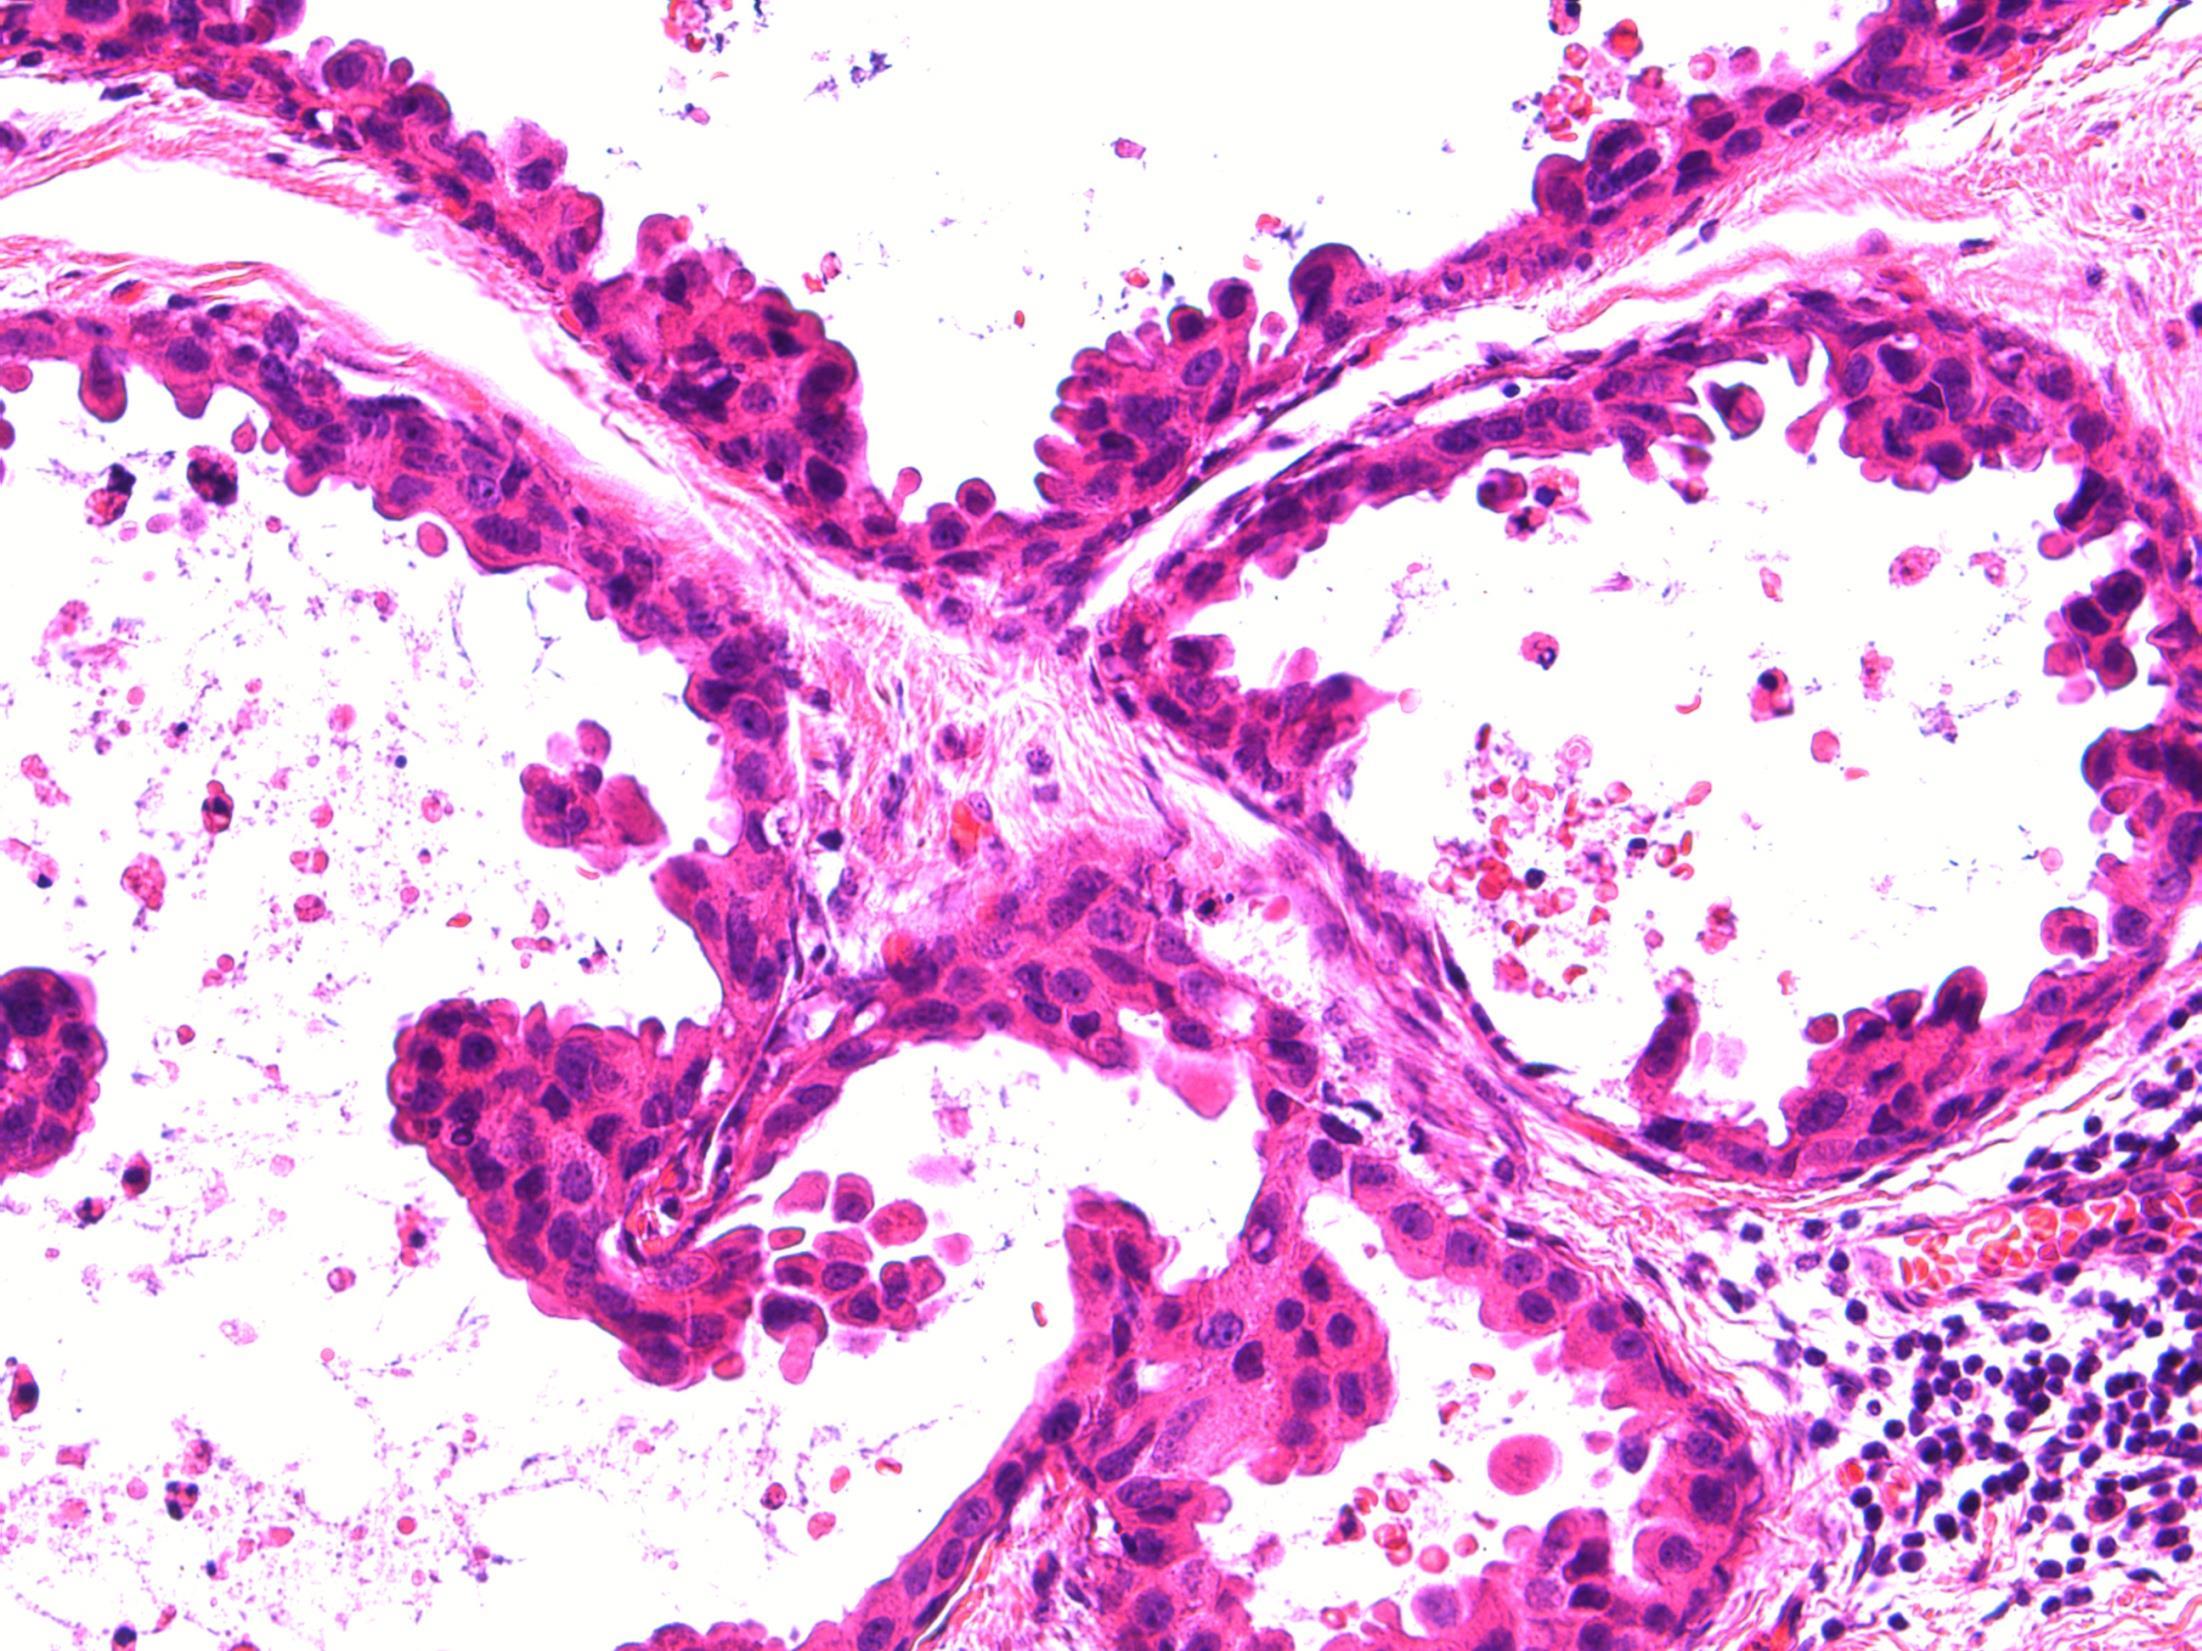

Case 12 • 41F with a breast implant. Mammogram showed multifocal microcalcifications. Initial core biopsy B1, repeat core biopsy B5a. Mastectomy performed – section from this specimen.

• Breast – High grade DCIS + displaced epithelium + silicone granuloma

Case 12

Description: Breast tissue showing areas of high grade DCIS of flat/micropapillary type. Also areas of foamy macrophages with giant cells. Focally can see a fibrous tract containing small groups of bland epithelial cells. No evidence of invasive malignancy.

seen following previous needling –

Diagnosis: High grade DCIS + displaced epithelium + silicone granuloma Plan: Correlate with clinical findings, radiology, previous biopsy (B5a) and cytology. Check other blocks for invasive malignancy. Measure distance to margins. Breast MDT discussion. Comments: Epithelial displacement

Small and dispersed clusters of epithelial cells seen within the fibroblastic reactive stroma

Can simulate malignancy

p63 and SMM – negative Silicone granuloma associated with breast implants (as in this case).